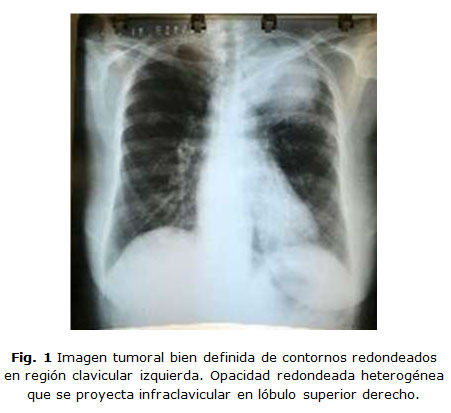

Los estudios de imagenología mostraron en el RX de Tórax una imagen tumoral bien definida de contornos redondeados en región clavicular izquierda. Opacidad redondeada heterogénea, que se proyecta infra clavicular en lóbulo superior derecho. (Figura 1)

Las imágenes mostradas resultan muy sugestivas de una  lesión tumoración de vértice de pulmón las cuales  asociadas a manifestaciones generales constitucionales y extra-articulares resultan sustentables para establecer  el diagnóstico de  cáncer de pulmón con posibles lesiones metastásicas contra laterales. No obstante resultan varios los posibles diagnósticos a diferenciar por lo cual constituye un reto la toma de decisiones e imponer un tratamiento adecuado atendiendo al riesgo beneficio.